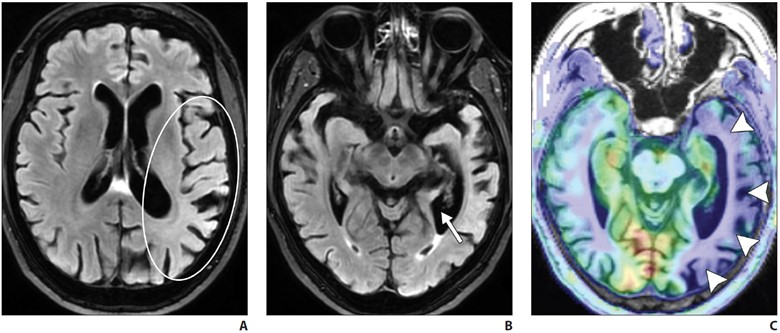

Logopenic variant primary progressive aphasia (PPA) is the most common atypical presentation of early-onset AD, characterized by predominant language dysfunction. Impaired single-word retrieval and impaired repetition are the core features of logopenic variant PPA [18]. There is a high rate of amyloid and tau positivity [18]. Atrophy is centered at the left temporoparietal junction and the left inferior parietal and superior temporal regions, including the supramarginal and angular gyri, and is associated with concomitant hippocampal volume loss (Fig. 4).

A–C, Axial FLAIR (A and B) and axial arterial spin-labeling (ASL) (C) MR images of patient with impaired word retrieval and repetition show left inferior parietal and superior temporal region atrophy, suggested by asymmetric sulcal widening on FLAIR MR image (oval, A) compared with that seen on ASL image (C). Left temporal atrophy was also suggested by asymmetric widening of left temporal horn (arrow, B). Hypoperfusion in involved regions (arrowheads, C) is likely due to underlying hypometabolism.

FDG PET shows temporoparietal hypometabolism (left greater than right) [18].